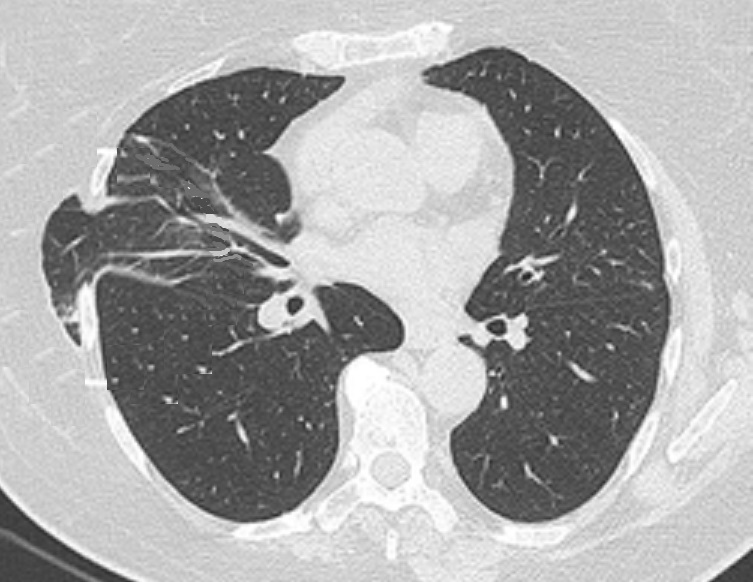

Même cas en coupe TDM axiale

,

fenêtre parenchymateuse |